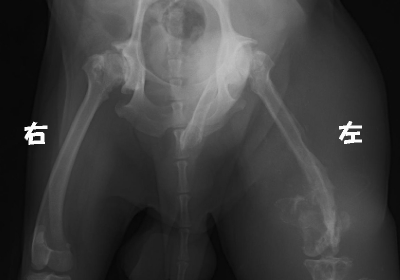

Step 05. レントゲン

上記の検査は、『腫瘍の正体を知るための検査』でした。レントゲンやエコーは、『腫瘍があるかどうか』の検査です。体内の腫瘍を探したり、他の臓器にできた腫瘍が肺転移していないか探したりが目的となります。

組織球肉腫

非常に悪性度の高い腫瘍の1つです。腫瘍によって左脚の骨が破壊され骨折しています。

周りの組織も右脚の倍くらいに腫れ上がっています。